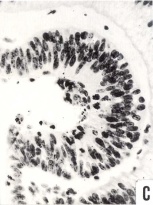

Section through the lens - Figure

Section through the lens - Drawing

Section through the lens - Section